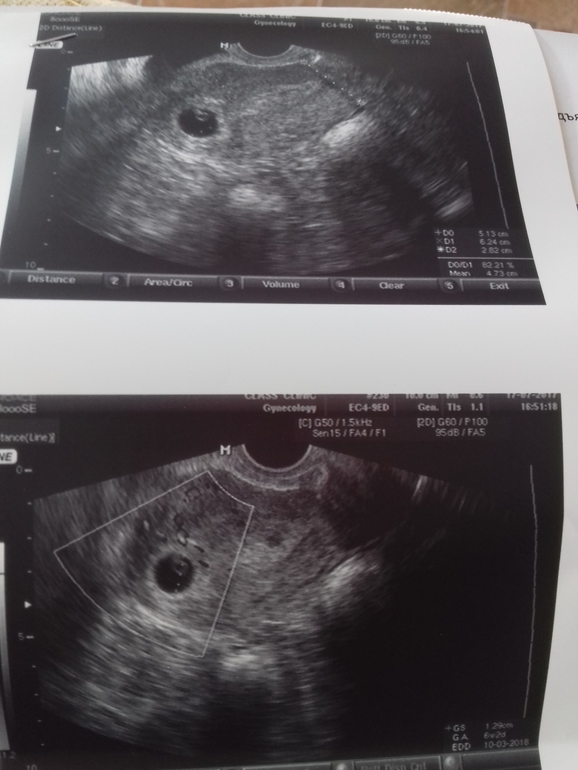

Узи 6недель и 4 дня

Беременность- 1 триместр ( только до 10 недель)Девочки всем привет. Сходила я на узи не выдержала до семи недель,т.к. слева болело очень. Вот нас нашли. Размер d=1.29см с жм и эмбрионом.(серцебиение визуализируется нечетко) Все соответствует сроку. Выдохнула.

В ля кистозное жт,поэтому болит.

Я беспокоюсь по поводу,нашла маленькую гимотомку-это страшно,что делать? Очень переживаю.

И еще в матке есть одна точка до 5мм,она сказала либо это жид-ть скопившиеся в эндике,либо плод,который не развился и погиб. Сказала придти через неделю посмотрим еще. У кого мож было подобное?